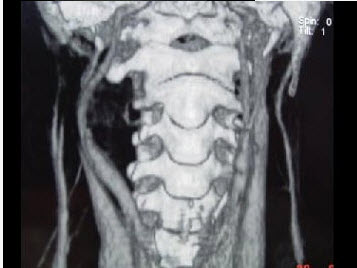

男,41岁,右侧咽部不适两年余,有异物感,声音嘶哑,CT如图所示,最可能诊断为()。

A、颈动脉体瘤

B、咽旁转移癌

C、咽旁淋巴瘤

D、小唾液腺瘤

E、咽旁神经鞘膜瘤

E